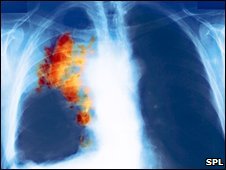

سرطان ریه از نوع "سلول کوچک" به سختی قابل تشخیص است

سرطان ریه یکی از کشنده ترین سرطان هاست و نوعی از آن که به "سلول کوچک" موسوم است و 20 درصد کل موارد این سرطان را تشکیل می دهد به سختی قابل تشخیص است. تنها 3 درصد بیماران مبتلا به این نوع سرطان ریه پنج سال دوام می آورند.

این نوع سرطان ریه خیلی سریع منتشر می شود بنابراین عمل جراحی گزینه ای موثر برای درمان آن نیست.